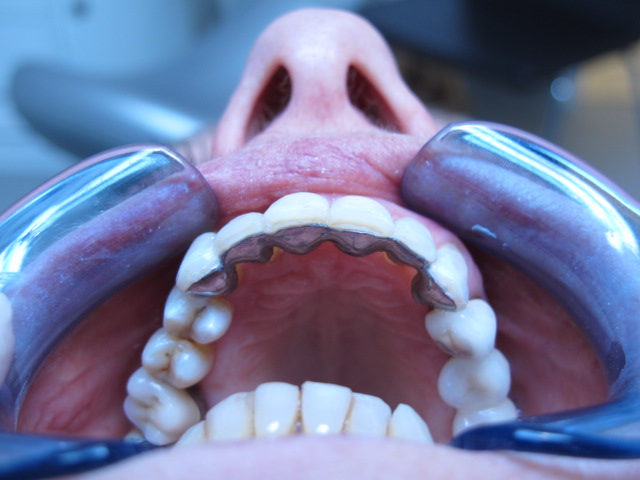

Arcade mandibulaire avant traitement orthodontique, séquelles de maladie parodontale

Après traitement orthodontique et réalisation d’une attelle fibrée (courtoisie Dr Patrick Fournier)